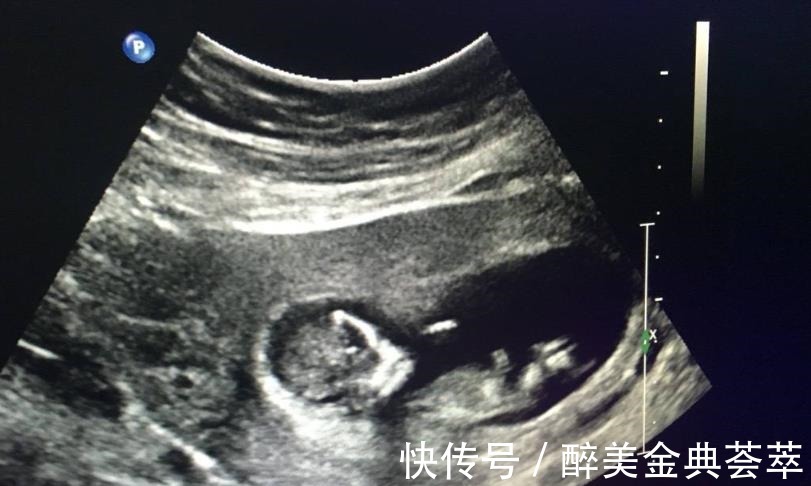

胎儿的性别是从受精卵开始就已经决定了,在孕初期无法看出胎儿的性别,而到了孕十二周,胎儿的性别特征才会一点点显现出来。怀孕十二周,腹中胎儿的不同性别有哪些区别?孕十二周,由于胎儿还处在生长发育阶段,其身长只有约9厘米,胎重23g左右,相当于3颗草莓的重量。这个阶段我们还只能看到胎心和胎芽,其他器官都还未发育成熟,而胎儿的性别器官已经开始发育,不过都还都未发育完全,因此就算此时通过B超检察胎儿性别,也不一定准确。并且医院有明确规定:不允许通过B超手段,检查胎儿性别,并且不允许医生提前告知胎儿性别,因此就算医生看得出来,也是会“守口如瓶”的。

5、孕16周性别显现比较明显孕十六周胎儿的性别器官才完全发育成熟,这时B超就可以相对准确地看出胎儿的性别了,但也是需要一些运气的,因为有时碰巧遇到胎儿背着身体或四肢遮挡住性别器官,那就没办法确认了。【 胃口|怀孕后,想知道胎儿性别是什么,可以尝试这些方法来鉴别】